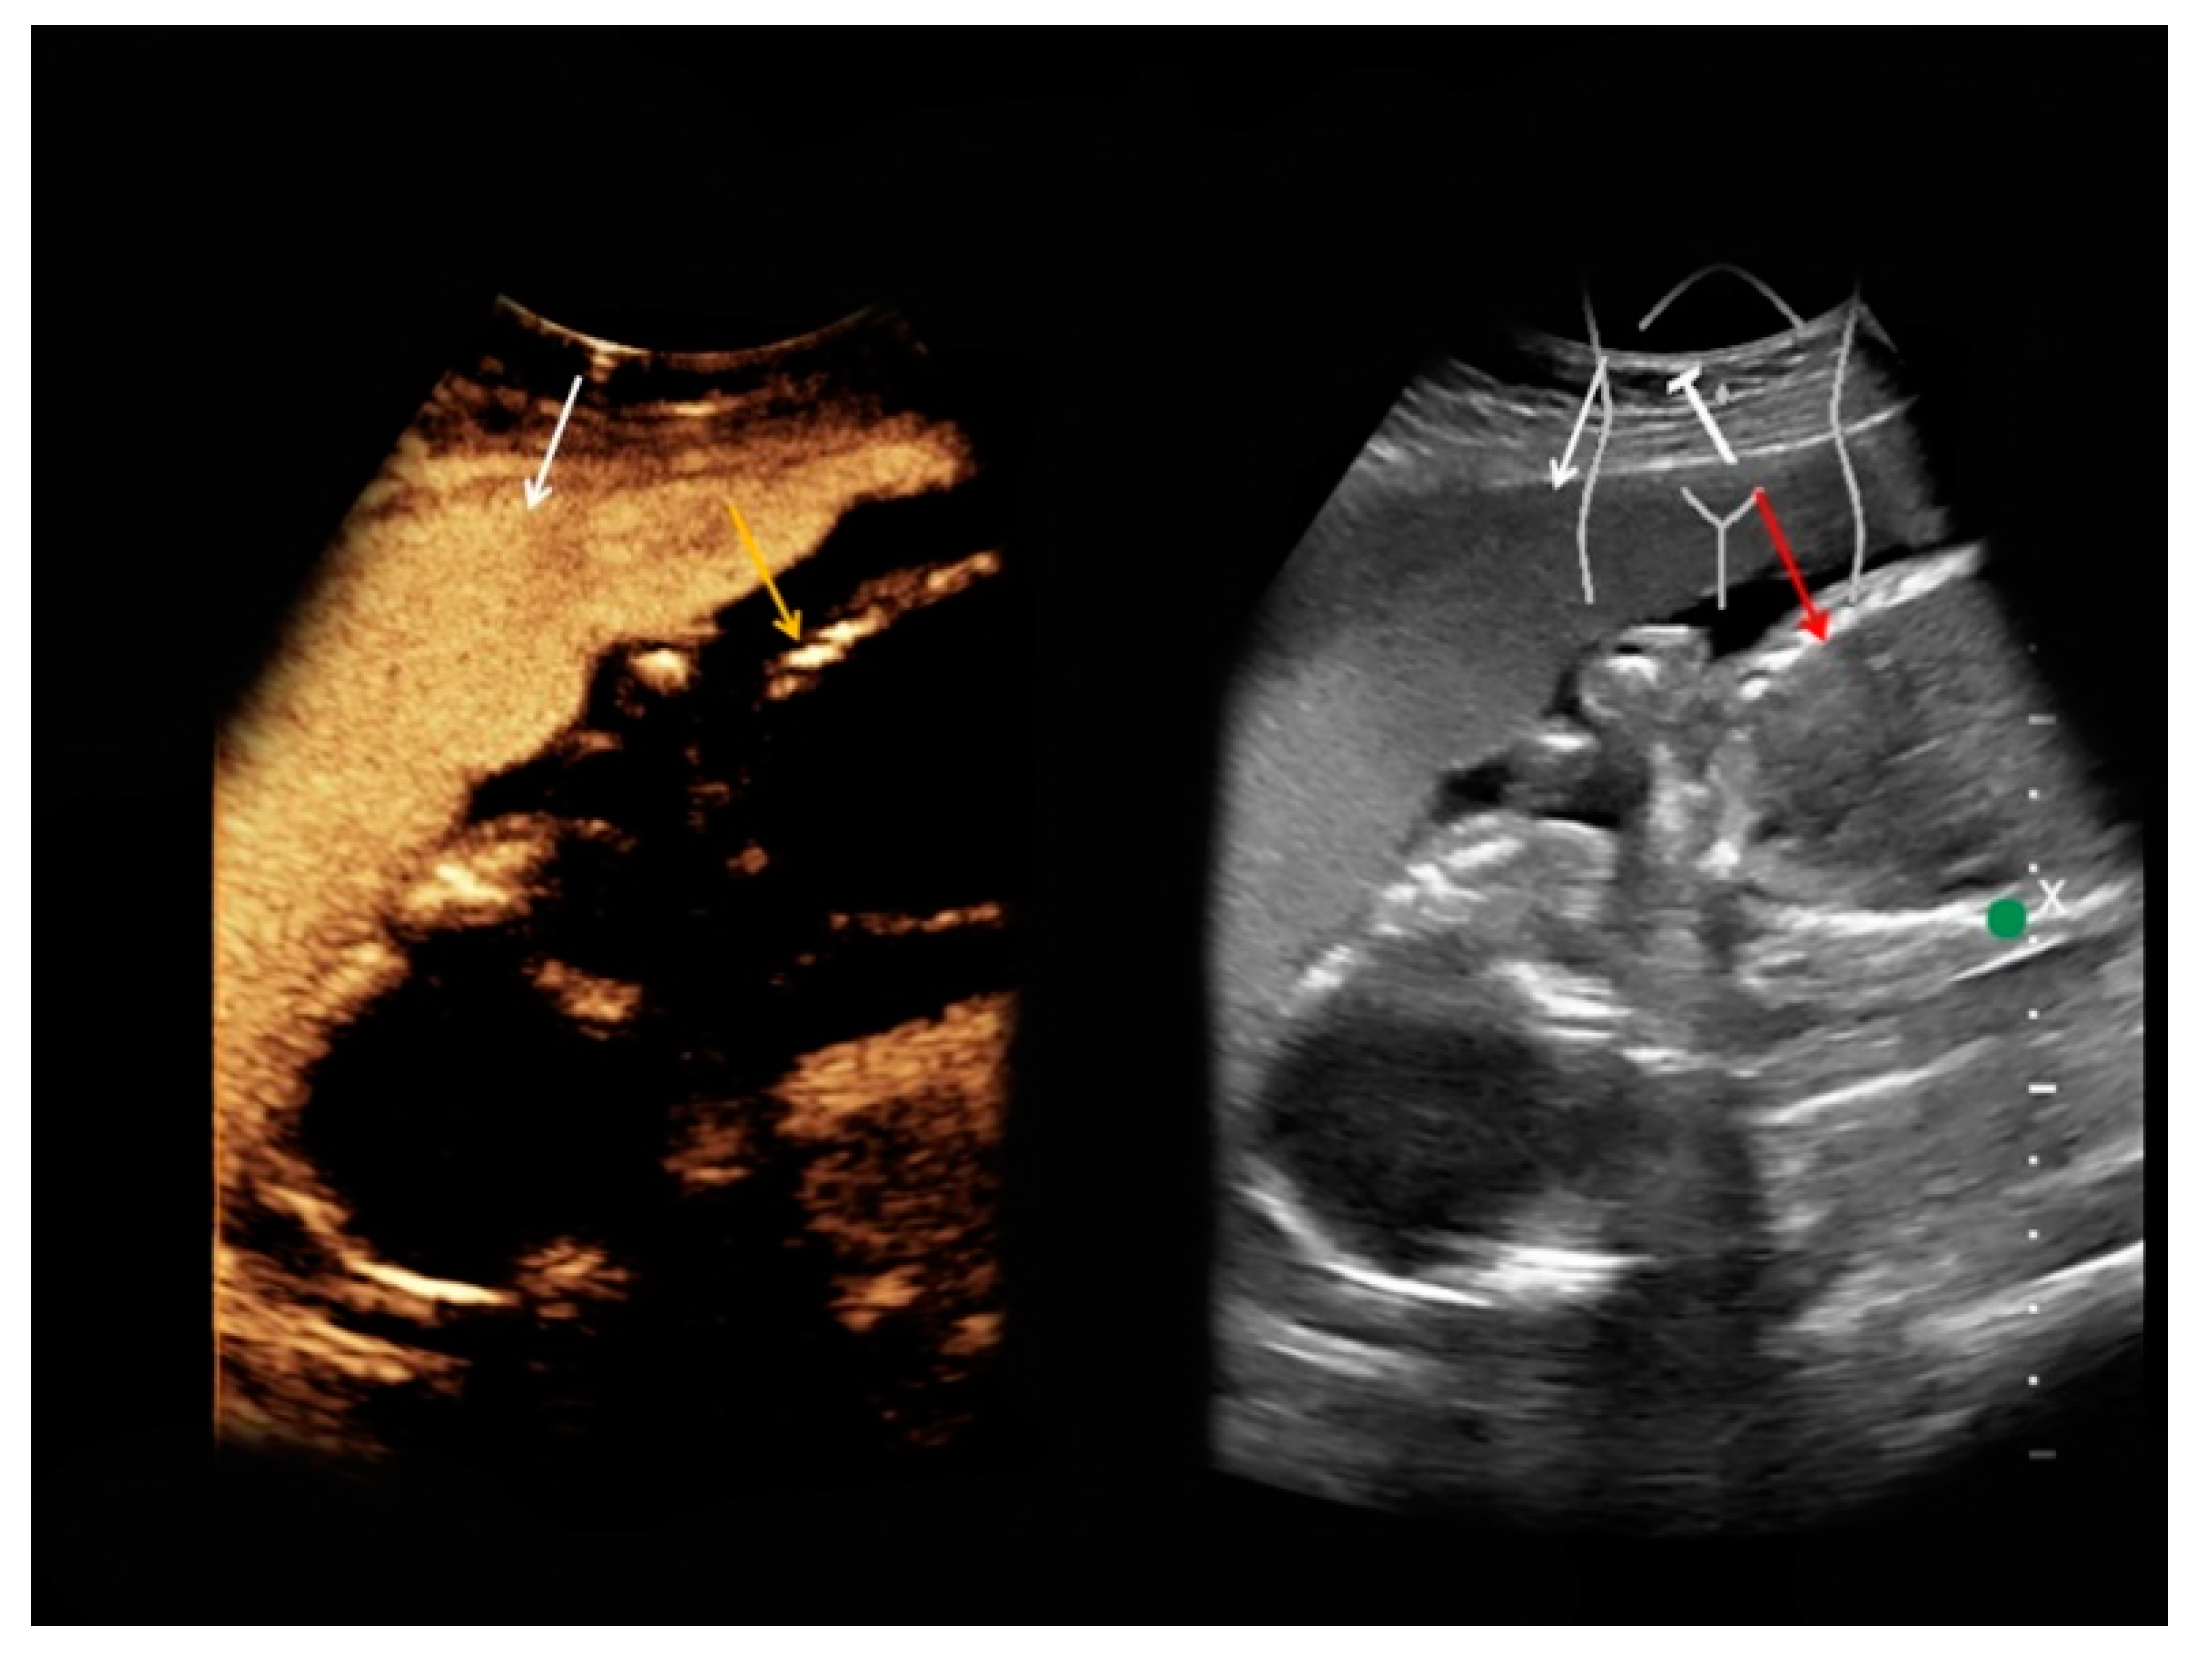

| #2 | 37 | 21 | Pyelonephritis, ruled out the presence of an abscess | B-mode: no abnormalities Doppler: no abnormalities CEUS: homogeneous contrast enhancement, no abscess | homogeneous, restricted diffusion, perirenal fluid collections |